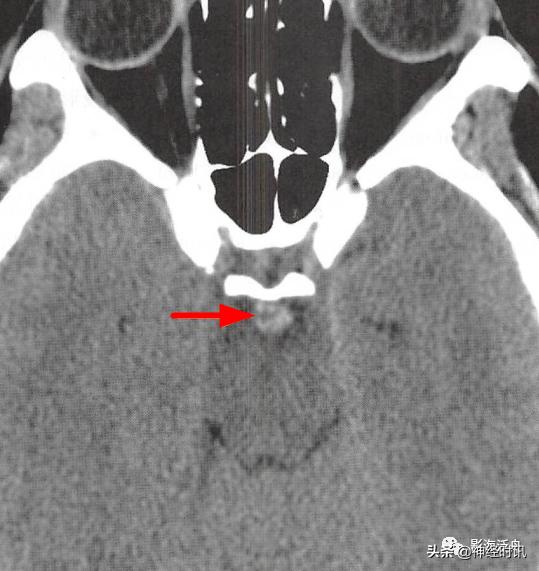

部分国外学者认为少量蛛血的常见部位位于大脑中脚之间的脚间池内(红箭),笔者尚未遇到过(是不是漏掉了?)。此种类型的少量蛛血常可引起患者“雷击样头痛”,且血管造影几乎均为阴性,如果在急诊CT平扫中漏诊此型蛛血,将会对临床诊断造成极*麻大**烦,因为可逆性血管收缩综合征等也会出现类似的剧烈头痛症状。